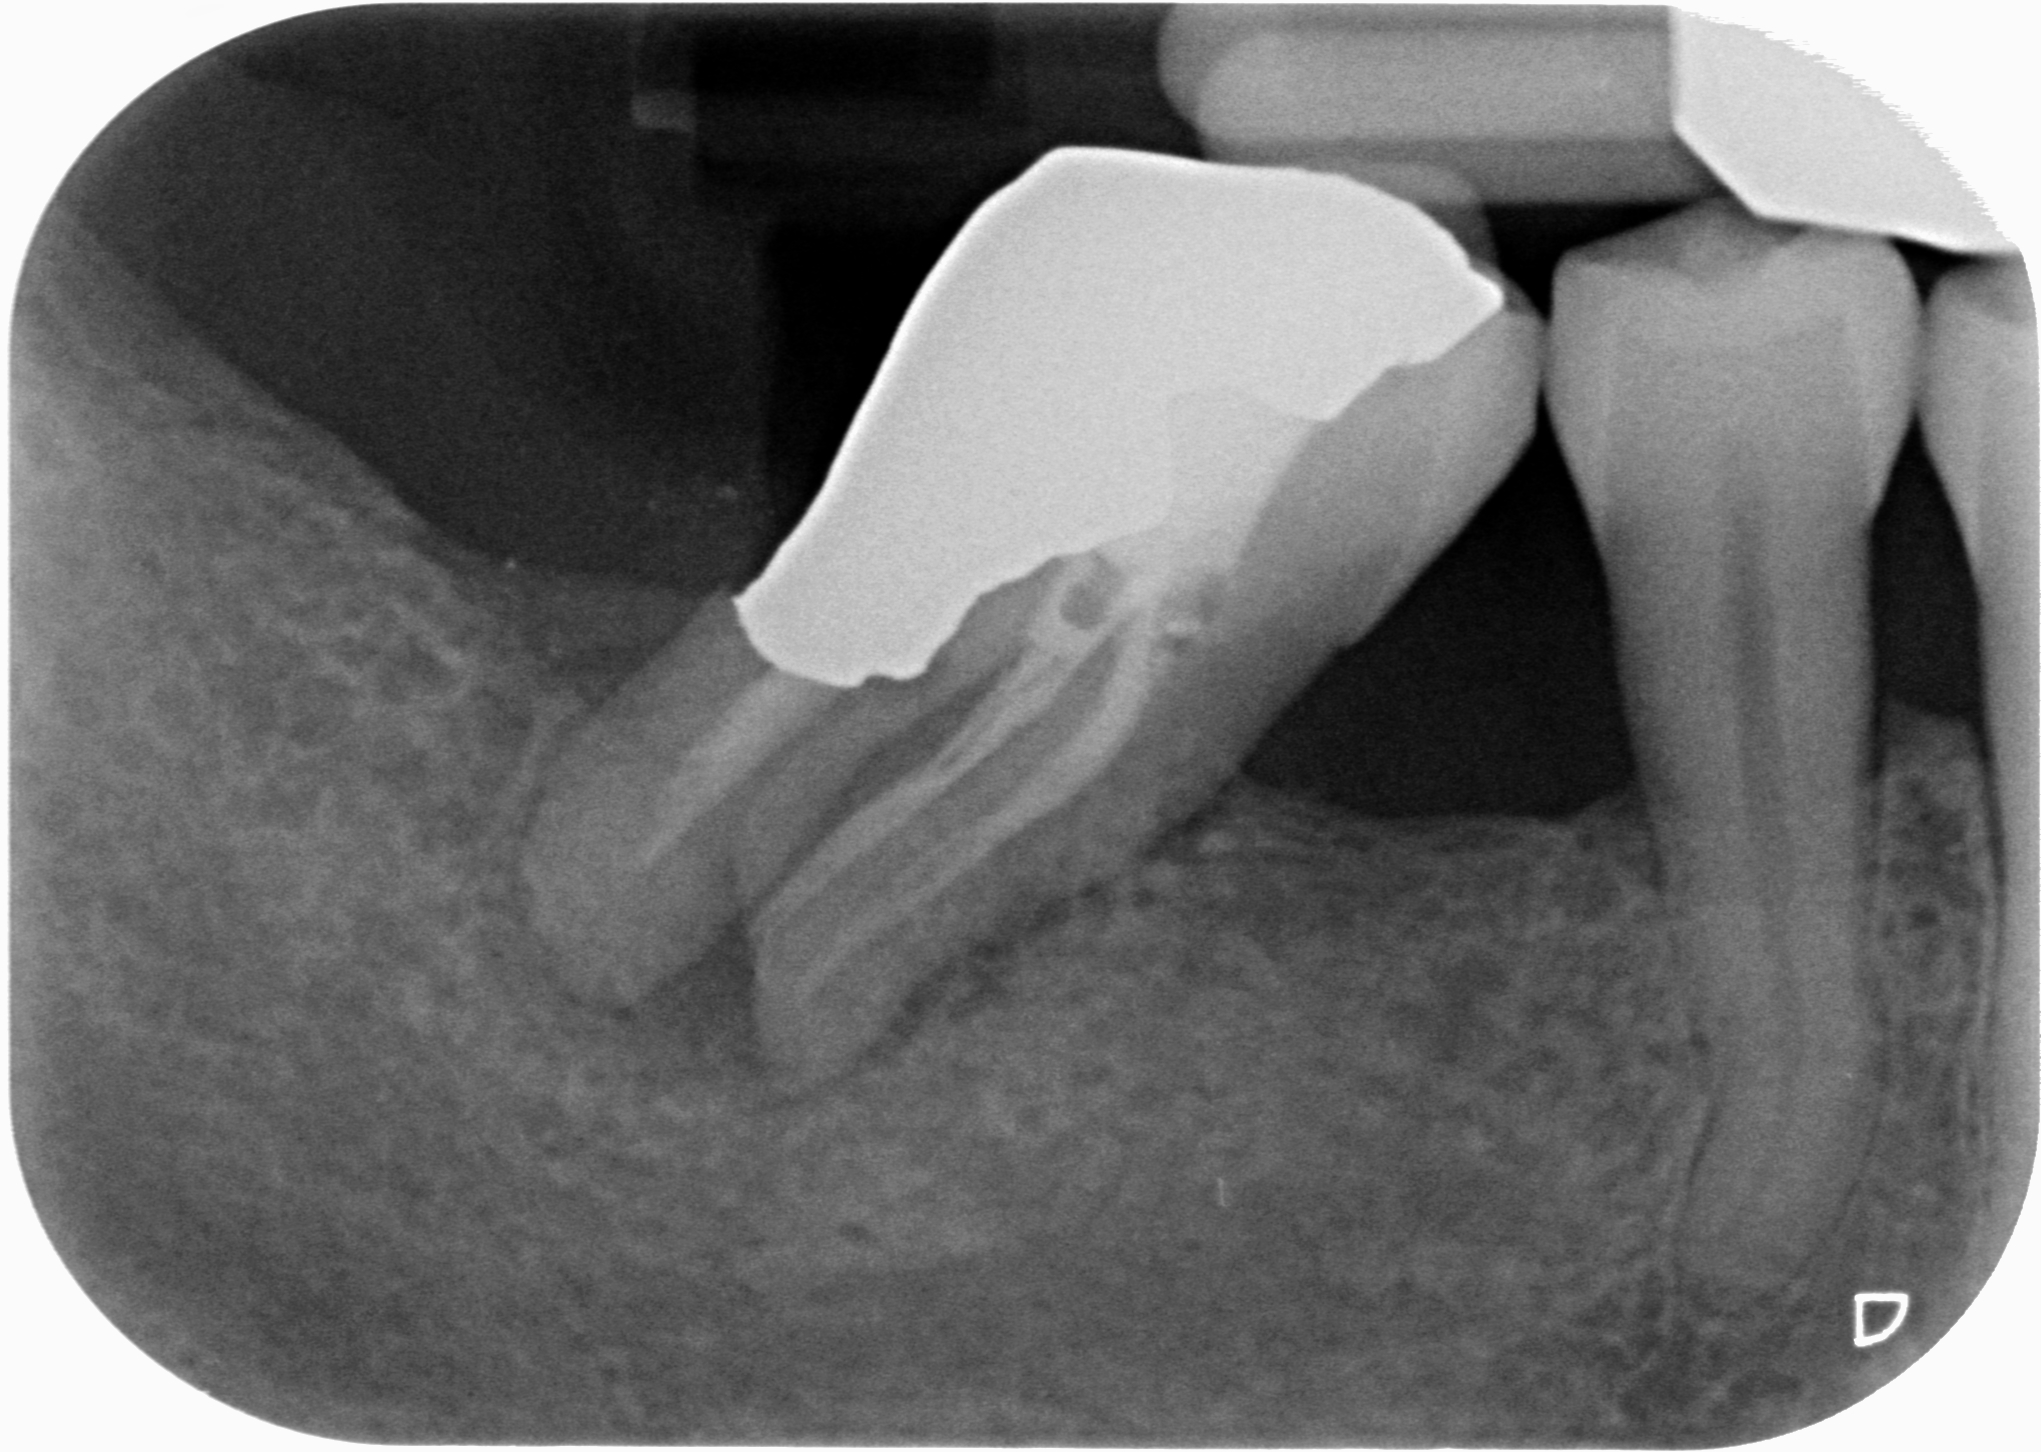

Se invadere l’ampiezza biologica massacra l’osso e genera tasche spiegami perchè in queste due rx scattate a 4 anni di distanza tra loro, l’osso distale al 4.7 mesializzato, che sarà da estrarre per altri motivi, sia sempre uguale, con un risentimento legato alla carie primaria che c’era stata verosimilmente decenni prima…?

Il tutto con una amalgama ben più difficile da rifinire rispetto alla superficie di un composito flow!

Come puoi vedere dalle immagini qui sotto, il caso che ho mostrato nella rx precedente a 4 anni di distanza mostra che nè l’osso nè la papilla risentono di questo terribile insulto…